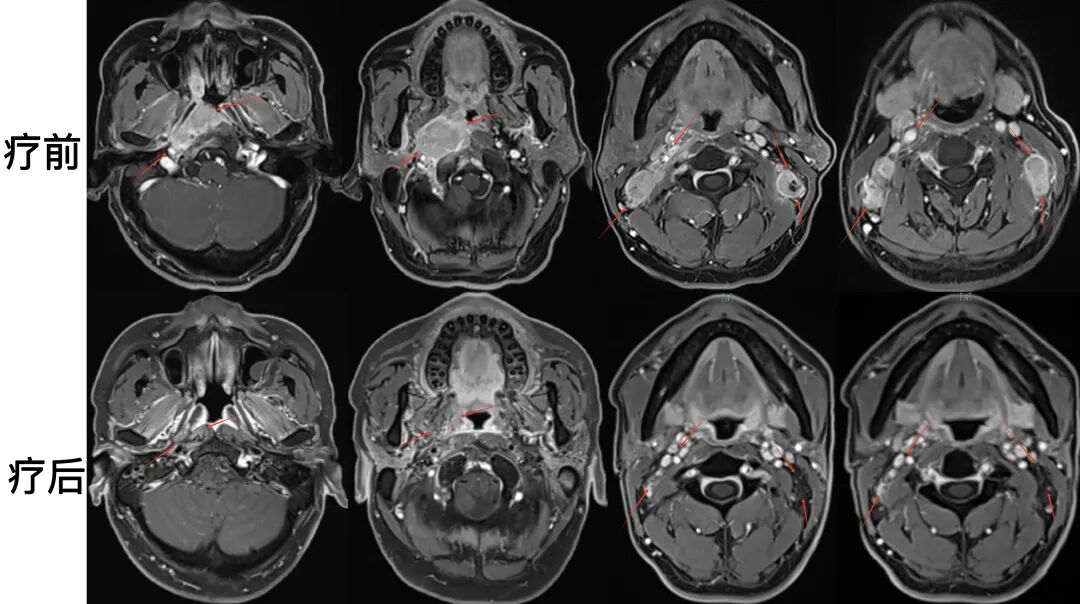

病例4:48歲男性患者,耳悶及頸部腫物起病。磁共振檢查可見雙側(cè)鼻咽頂部腫物,向后侵犯斜坡骨皮質(zhì);雙側(cè)頸部多發(fā)轉(zhuǎn)移腫大淋巴結(jié),為局部晚期鼻咽癌。

圖注:治療前后比對(duì)。上排為治療前,可見鼻咽腫物向前侵及翼突,向后累及斜坡;側(cè)咽后間隙及雙側(cè)頸部多發(fā)腫大淋巴結(jié)。下排為治療后,鼻咽區(qū)腫瘤病灶完全消失,頸部轉(zhuǎn)移淋巴結(jié)基本消失。